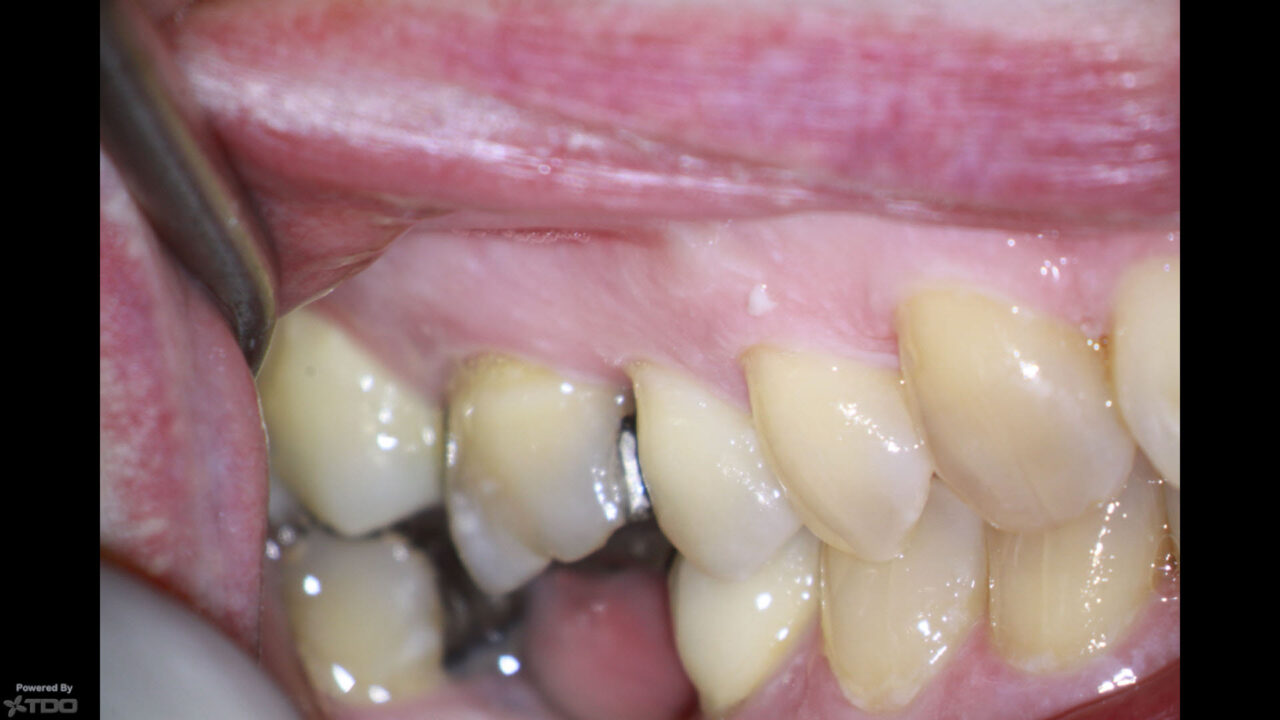

Plunger Cusp Examples . Root proximity problem that precludes restoration of a carious lesion. Cusps that tend to forcibly wedge food into interproximal embrasure are known as plunger cusps. The plunger cusp effect may occur with wear as indicated above, or may be the result of a shift in. If the marginal ridges were uneven, the more prominent ridge should be reduced. • cusps that tend to forcibly wedge food interproximally are known as plunger cusps. If a plunger cusp was detected, it should be. Stabilization of dental malalignment, malocclusion, or occlusal disharmony. • the plunger cusp effect may occur with wear , as indicated, or may be the. The presence of a plunger cusp requires occlusal adjustment in order to prevent food packing. As the teeth wears down and flattened surfaces replace the normal convexities, the wedging effect of opposing cusp is exaggerated, and food impaction results. This article reviews the diagnosis and treatment of cracked teeth, and explores common clinical examples of cracked teeth, such as. Wherever possible, the cusp should be reshaped to provide contact with an.

The presence of a plunger cusp requires occlusal adjustment in order to prevent food packing. Cusps that tend to forcibly wedge food into interproximal embrasure are known as plunger cusps. Root proximity problem that precludes restoration of a carious lesion. This article reviews the diagnosis and treatment of cracked teeth, and explores common clinical examples of cracked teeth, such as. As the teeth wears down and flattened surfaces replace the normal convexities, the wedging effect of opposing cusp is exaggerated, and food impaction results. If the marginal ridges were uneven, the more prominent ridge should be reduced. • the plunger cusp effect may occur with wear , as indicated, or may be the. Wherever possible, the cusp should be reshaped to provide contact with an. The plunger cusp effect may occur with wear as indicated above, or may be the result of a shift in. If a plunger cusp was detected, it should be.

Plunger Cusp Examples If a plunger cusp was detected, it should be. The plunger cusp effect may occur with wear as indicated above, or may be the result of a shift in. Wherever possible, the cusp should be reshaped to provide contact with an. Cusps that tend to forcibly wedge food into interproximal embrasure are known as plunger cusps. • cusps that tend to forcibly wedge food interproximally are known as plunger cusps. Stabilization of dental malalignment, malocclusion, or occlusal disharmony. This article reviews the diagnosis and treatment of cracked teeth, and explores common clinical examples of cracked teeth, such as. If the marginal ridges were uneven, the more prominent ridge should be reduced. As the teeth wears down and flattened surfaces replace the normal convexities, the wedging effect of opposing cusp is exaggerated, and food impaction results. Root proximity problem that precludes restoration of a carious lesion. • the plunger cusp effect may occur with wear , as indicated, or may be the. The presence of a plunger cusp requires occlusal adjustment in order to prevent food packing. If a plunger cusp was detected, it should be.